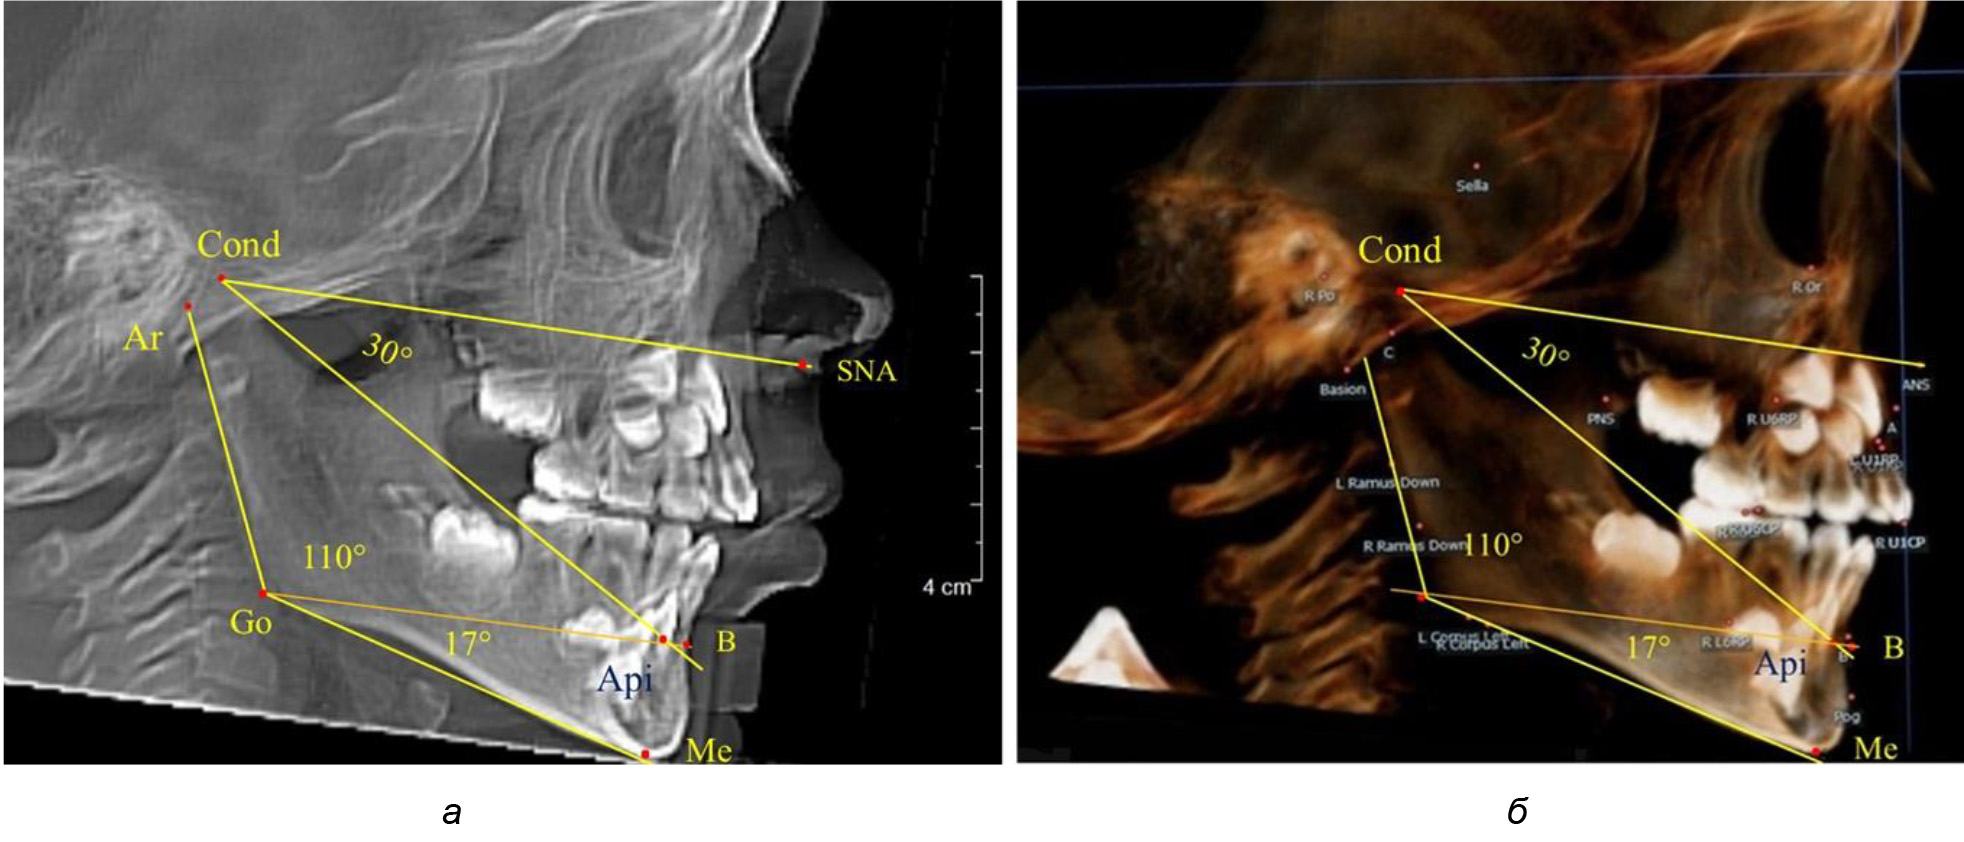

Особенность анализа телерентгенограммы в периоде сменного прикуса заключалась в том, что наслоение зачатков постоянных зубов затрудняло определение апикальной точки нижнего резца. В подобных случаях использовали метод совмещенного анализа телерентгенограммы с фрагментом томограммы, на котором, также как и на телерентгенограмме, определяли положение резцовой и апикальной точек с построением условной вертикали, которая служила ориентиром для совмещения фрагментов (рис. 2).

Рис. 2. Особенности совмещения телерентгенограммы с фрагментом томограммы в сменном прикусе

Таким образом, в периоде молочного прикуса с оптимальными окклюзионными соотношениями, несмотря на линейные размеры в вертикальном и сагиттальном направлении, которые, безусловно, меньше параметров взрослых людей, величина основного угла гнатической части лица SNA-Cond-Api соответствовала параметрам людей с полностью сформированным физиологическим прикусом постоянных зубов. Анализируя данные рентгенограмм детей в периоде сменного прикуса, отмечено, что величина основного угла гнатической части лица SNA-Cond-Api, так же как в молочном и постоянном прикусе, в норме составляла от 28 до 32°. В то же время угол нижней челюсти и его составляющие отличались вариабельностью параметров при различных показателях нижнечелюстного угла. Достоверных различий угла гнатической части после смены нижних медиальных резцов и прорезывания первых постоянных моляров (4 ребенка) не было; происходил очередной этап подъема высоты прикуса и увеличение линейных размеров костей гнатической части, однако угловые параметры были относительно стабильны. После смены всех резцов и замены первых молочных моляров первыми премолярами (6 человек) увеличивались линейные размеры при сохранившихся угловых показателях гнатической части лица (рис. 5).

Рис. 5. Варианты ТРГ после прорезывания ППМ и нижних резцов (а), всех резцов и первых премоляров (б)

Таким образом, в период сменного прикуса с оптимальными окклюзионными соотношениями, несмотря на увеличение линейных размеров в вертикальном и сагиттальном направлении, по сравнению с прикусом молочных зубов, величина основного угла гнатической части лица SNA-Cond-Api соответствовала показателям как постоянного, так и молочного прикуса с физиологическими окклюзионными соотношениями.